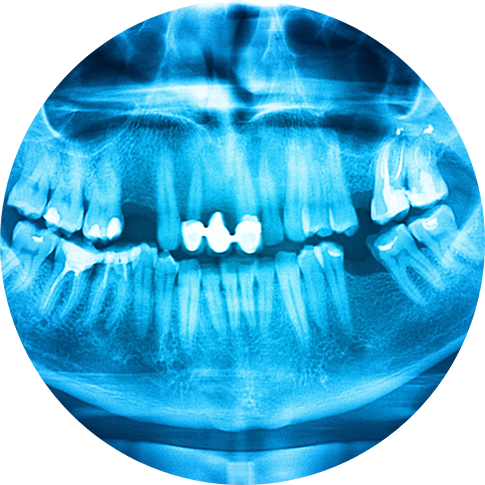

Bone grafting’s primary goal is simple: to restore strength and volume to the jawbone so that it has the needed density to support dental implants. It can also be an important step in the gum disease recovery process. The procedure involves using borrowed donor or synthetic bone tissue to fortify an area of the jaw that has deteriorated or shrunk, often due to years of missing teeth. The graft serves as a framework for new, living bone tissue to grow.

- You’re planning to get dental implants but have suffered jawbone deterioration due to years without teeth.

- Advanced gum disease has caused significant bone loss around existing teeth.